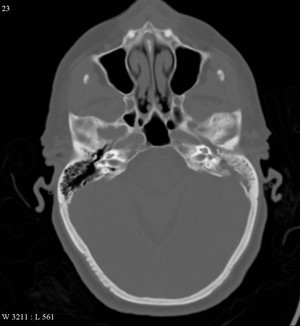

На рентгене сравнивается состояние здорового и больного уха, отмечается различная степень разрушения пневматического строения сосцевидного отростка, завуалированность полостей. В дальнейшем при дегенеративном процессе деструктивной формы мастоидита на снимке, видно просветление за счет разрушения перегородок и заполнения полостей грануляциями и гноем.

Типичное течение заболевания не отличается сложностью диагностики, но всякий нетипичный случай требует уточнения при рассмотрении. При этом берется во внимание совокупность стандартных признаков. Для точного диагностирования используется рентген, компьютерная томография или магниторезонансная терапия. Эти методы наиболее информативны, они могут дать сведения об интенсивности заболевания, степени дегенеративного процесса.